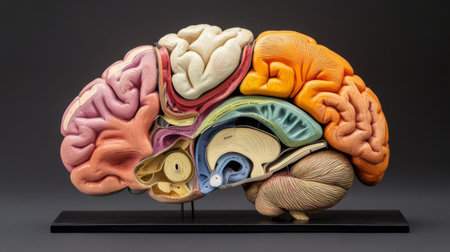

A model of the human brain, showing the different lobes and sections, with labels or color coding for an educational look, isolated on a clean background.

This detailed anatomical model of the human brain showcases its complex structure, perfect for educational settings or medical displays, enhancing learning and understanding.

A model of the human brain, showing the different lobes and sections, with labels or color coding for an educational look, isolated on a clean background.

This detailed cross-section of the human brain illustrates its anatomical features, making it ideal for educational purposes in neuroscience and medicine.

This detailed model showcases human brain anatomy, perfect for educational purposes. Ideal for classrooms, medical training, and scientific research.

A model of the human brain, showing the different lobes and sections, with labels or color coding for an educational look, isolated on a clean background.

A model of the human brain, showing the different lobes and sections, with labels or color coding for an educational look, isolated on a clean background.

A model of the human brain, showing the different lobes and sections, with labels or color coding for an educational look, isolated on a clean background.

A model of the human brain, showing the different lobes and sections, with labels or color coding for an educational look, isolated on a clean background.

This detailed human brain model showcases various regions and structures, ideal for educational purposes in neuroscience and psychology, emphasizing anatomical clarity.